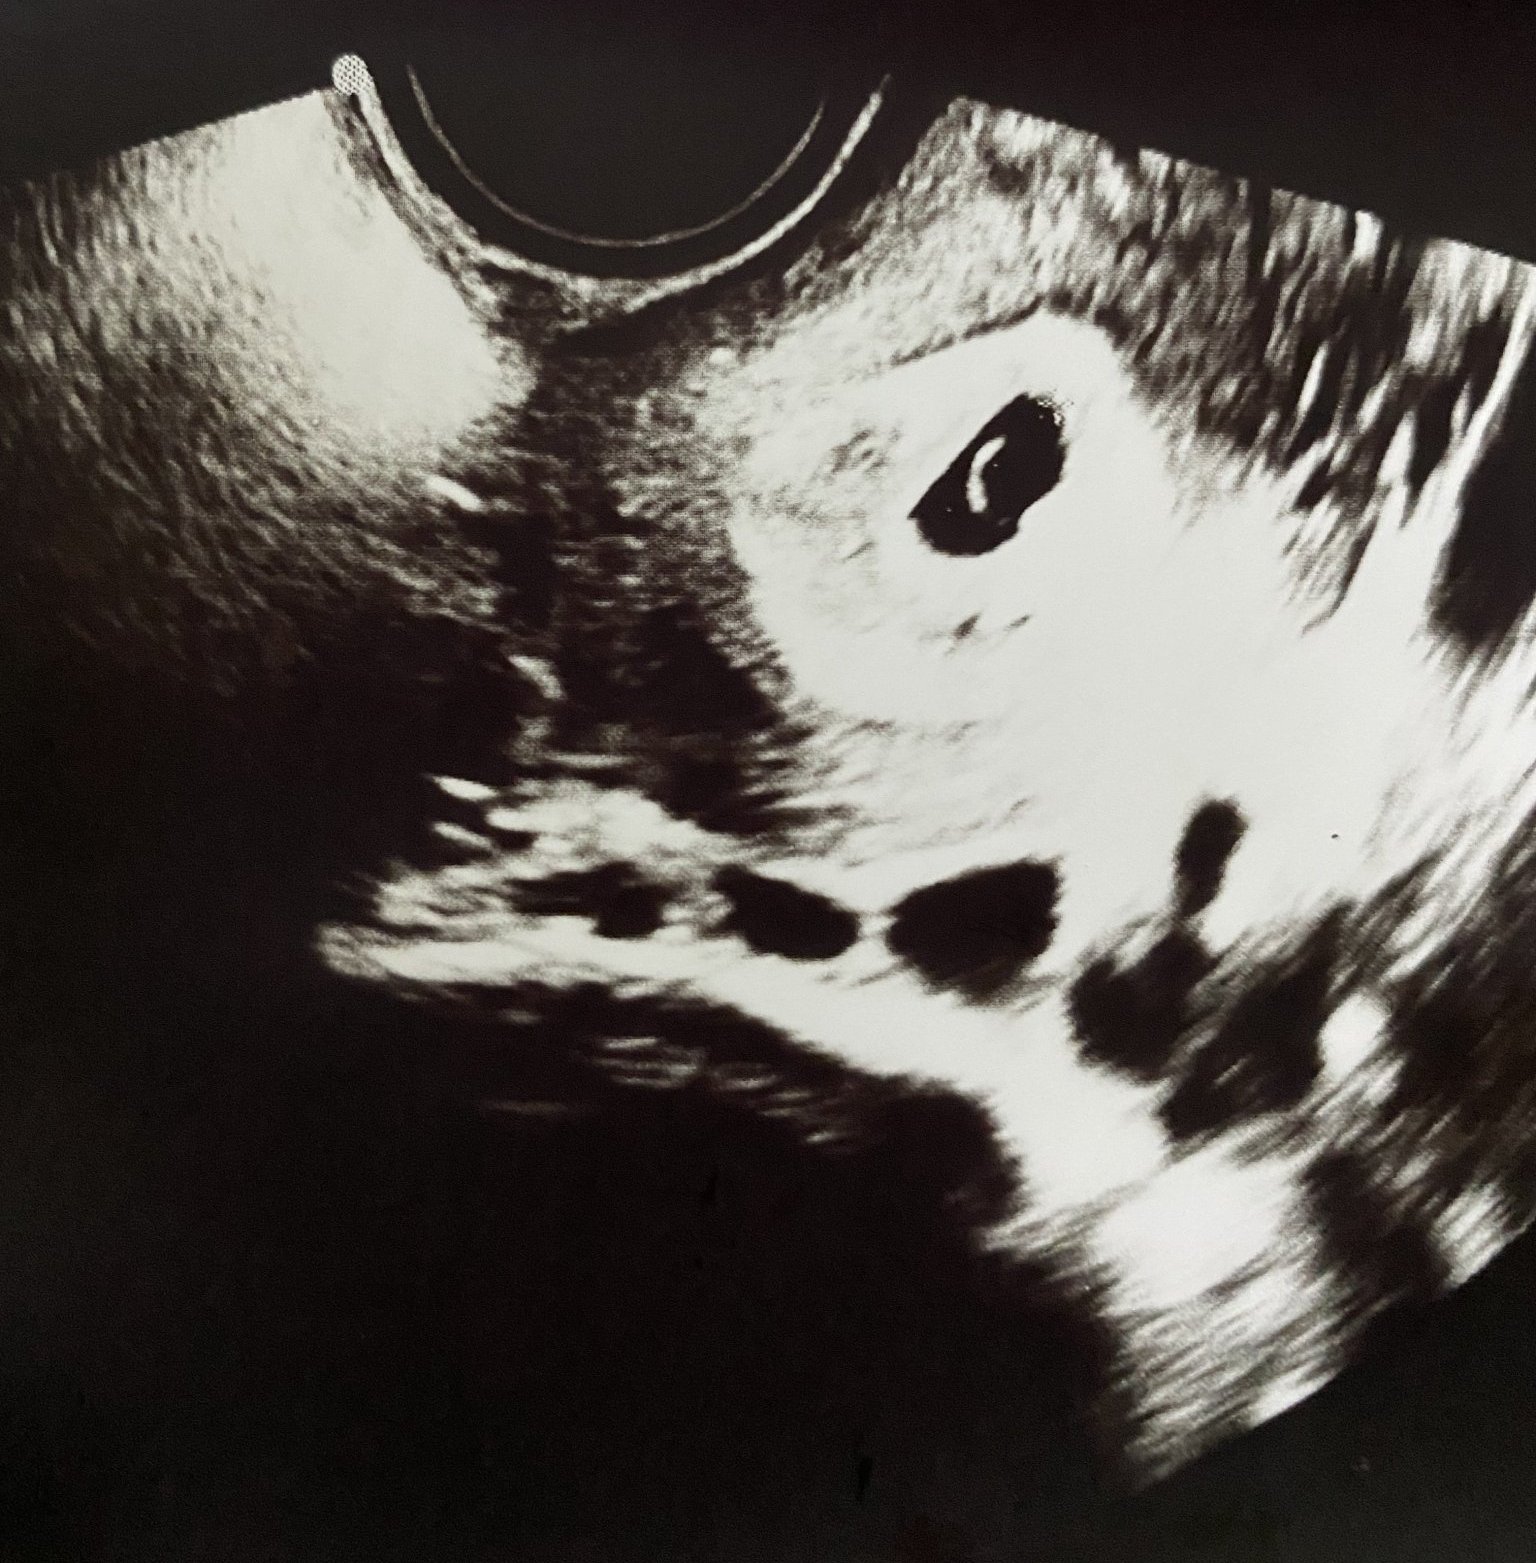

Здравейте. Пиша с огромно притеснение. Бременна съм в 7г.с, но след последния преглед по ехограф съм 5г.с. Все още не се вижда ембрион. Това са снимки от последните два прегледа.

На 28дни с редовен цикъл. На първата снимка 16.11 ( трябваше да съм 6г.с)

На втората снимка 23.11 ( по ехограф 5,3г.с) Само това ми каза

В 5 г. с по принцип не се вижда ембрион. Вижда се след 6та, т.е не 2,а една седмица не достига за да се правят изводи относно липсващата точица. Но да, може и да има такова закъснение. Има и ранна овулация. Просто теорията си е теория, а останалото е жив организъм със своята индивидуалност.